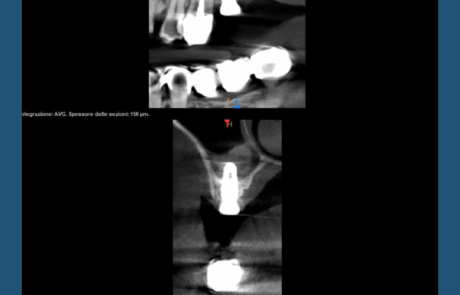

Quando scatti una nuova Conebeam per progettare un nuovo caso…e ti ritrovi, con piacere, davanti ad un impianto posizionato anni fa, perfettamente integrato, funzionale e stabile nel tempo.

Rigenerazione ossea verticale, rialzo di seno per via crestale, corona impeccabile.